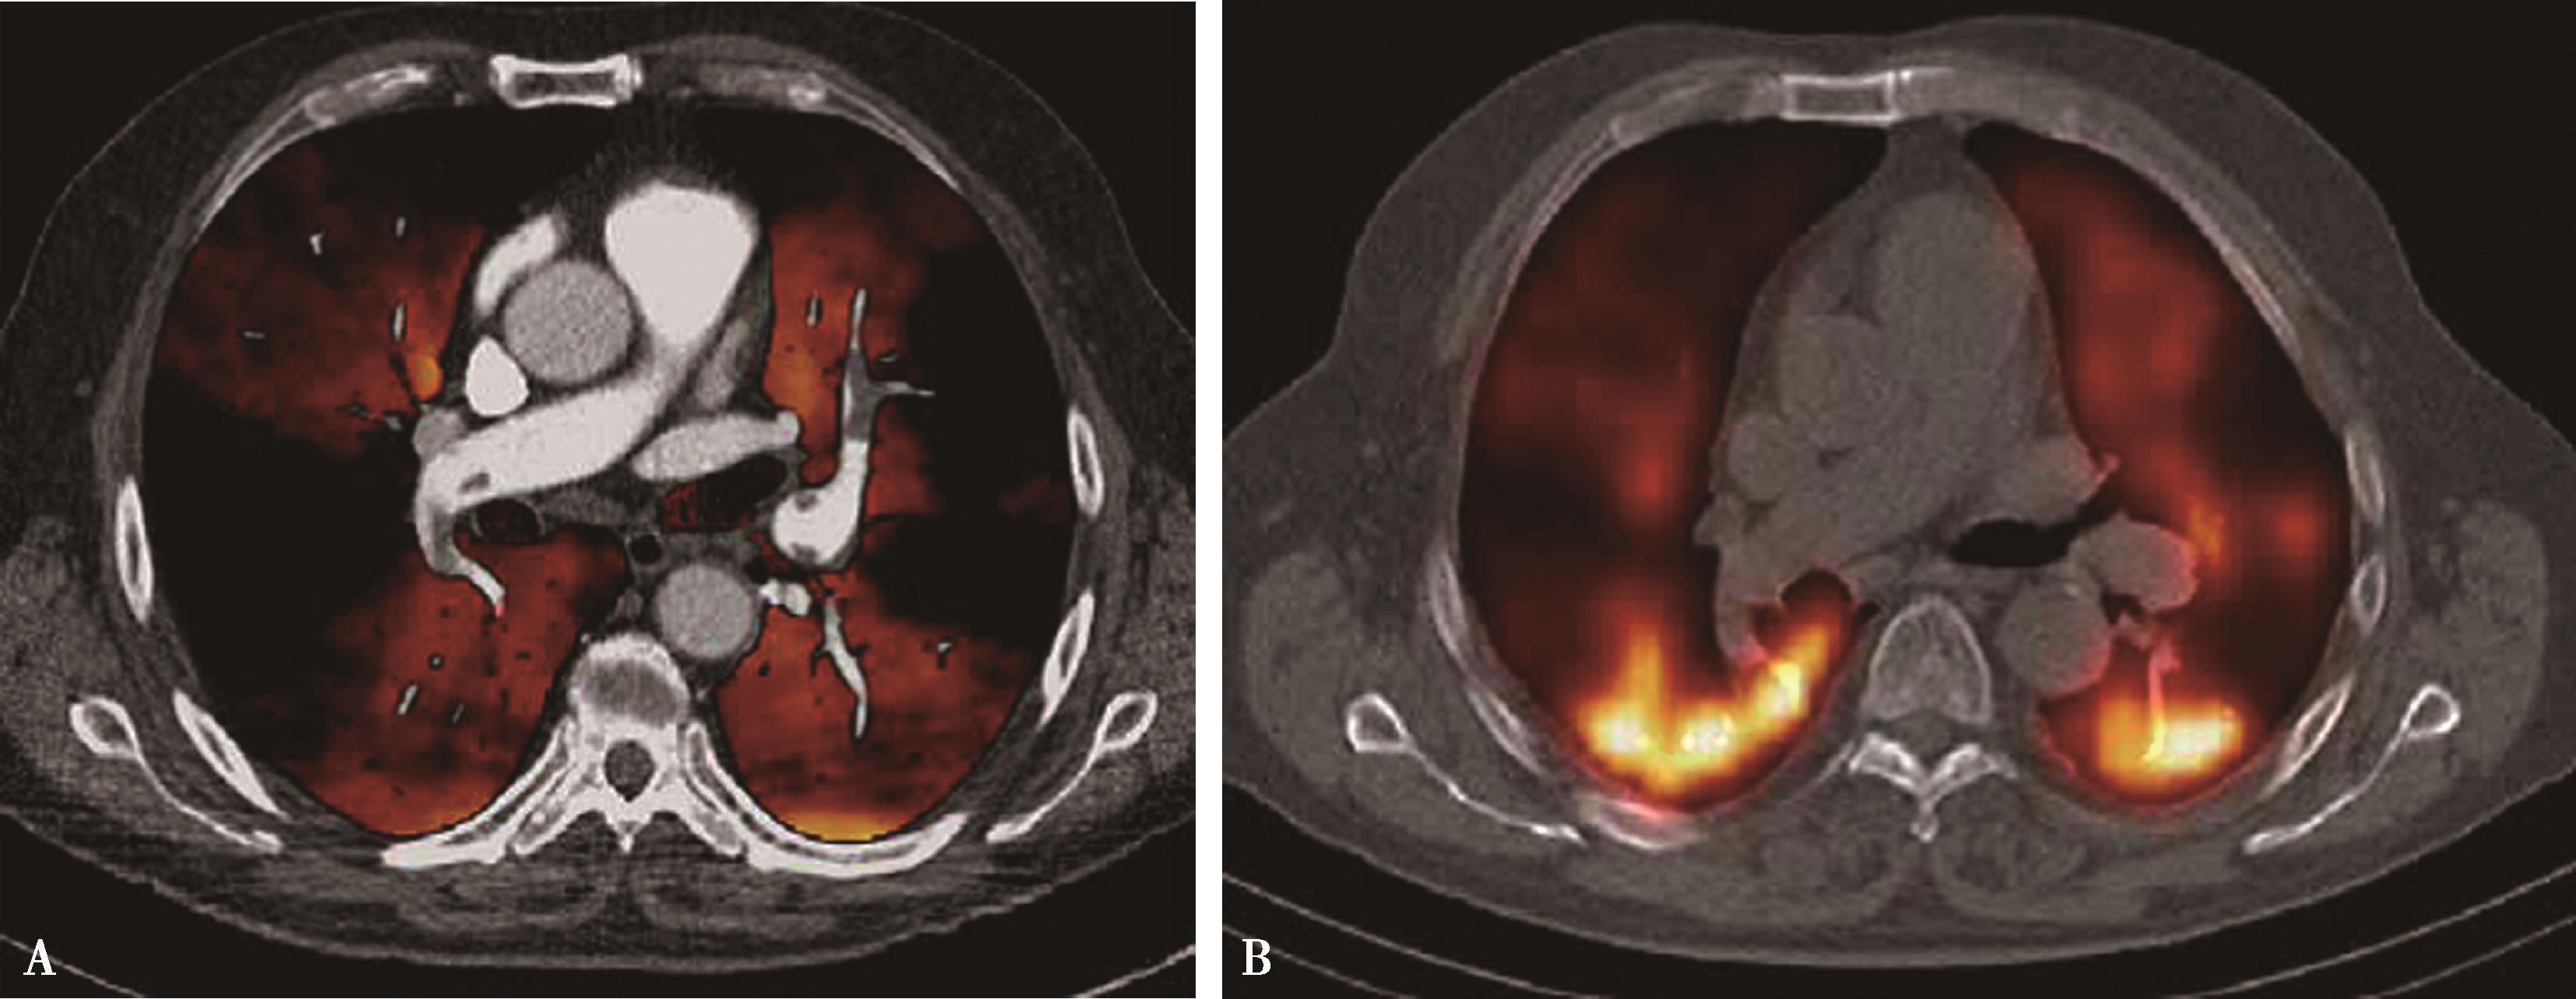

图8-3-1 急性肺栓塞肺灌注成像(EBCT资料)

A、 B.治疗前, 灌注量0.15ml/(min·ml); C、 D.治疗后, 灌注量改善1.4ml/(min·ml)

图8-3-2 正常肺组织

A.双能CT肺灌注成像(DELPI);B.核素 99m Tc-MAA SPECT/CT

图8-3-3 男,73岁,右肺下叶肺栓塞

A.双能CT肺灌注成像(DELPI);B.核素 99m Tc-MAA SPECT/CT。CT灌注扫描与核素检查结果一致

图8-3-4 男,69岁,双肺多发、急性肺栓塞

A.双能CT肺灌注成像(DELPI);B.核素 99m Tc-MAA SPECT/CT,CT灌注扫描与核素检查结果一致

1.CT肺灌注成像肺血流灌注研究(EBCT资料,图8-3-1)足侧及背侧肺段正常灌注量:2.42ml/(min·ml)。 头侧及腹侧肺段正常灌注量:2.19ml/(min·ml)。容积扫描(解剖诊断)与功能扫描在肺段以上水平一致率为85%~100%。功能扫描提供肺血流定量研究,为诊断及治疗提供更多信息,指导治疗,评价治疗效果。

2.CT肺灌注成像肺栓塞的诊断应用 CTPA及肺部灌注成像可以显示肺动脉管腔形态,可以显示肺栓塞所引起的肺动脉形态学变化,同时提供栓塞后肺组织微循环改变,并以灌注伪彩图的形式直观地显示栓塞引起的灌注缺损区,为诊断及治疗提供更多信息,指导治疗,评价治疗效果。但CT肺灌注成像不能直接显示栓子的部位和大小,诊断应该结合CTPA所显示的肺动脉狭窄及梗阻,做出诊断。但是,研究表明灌注扫描对检出亚分段的栓塞,可以提高CTPA诊断敏感性(20%),有重要价值。与核素对照研究,高度相关( r =0.884)(图8-3-2~图8-3-6)。